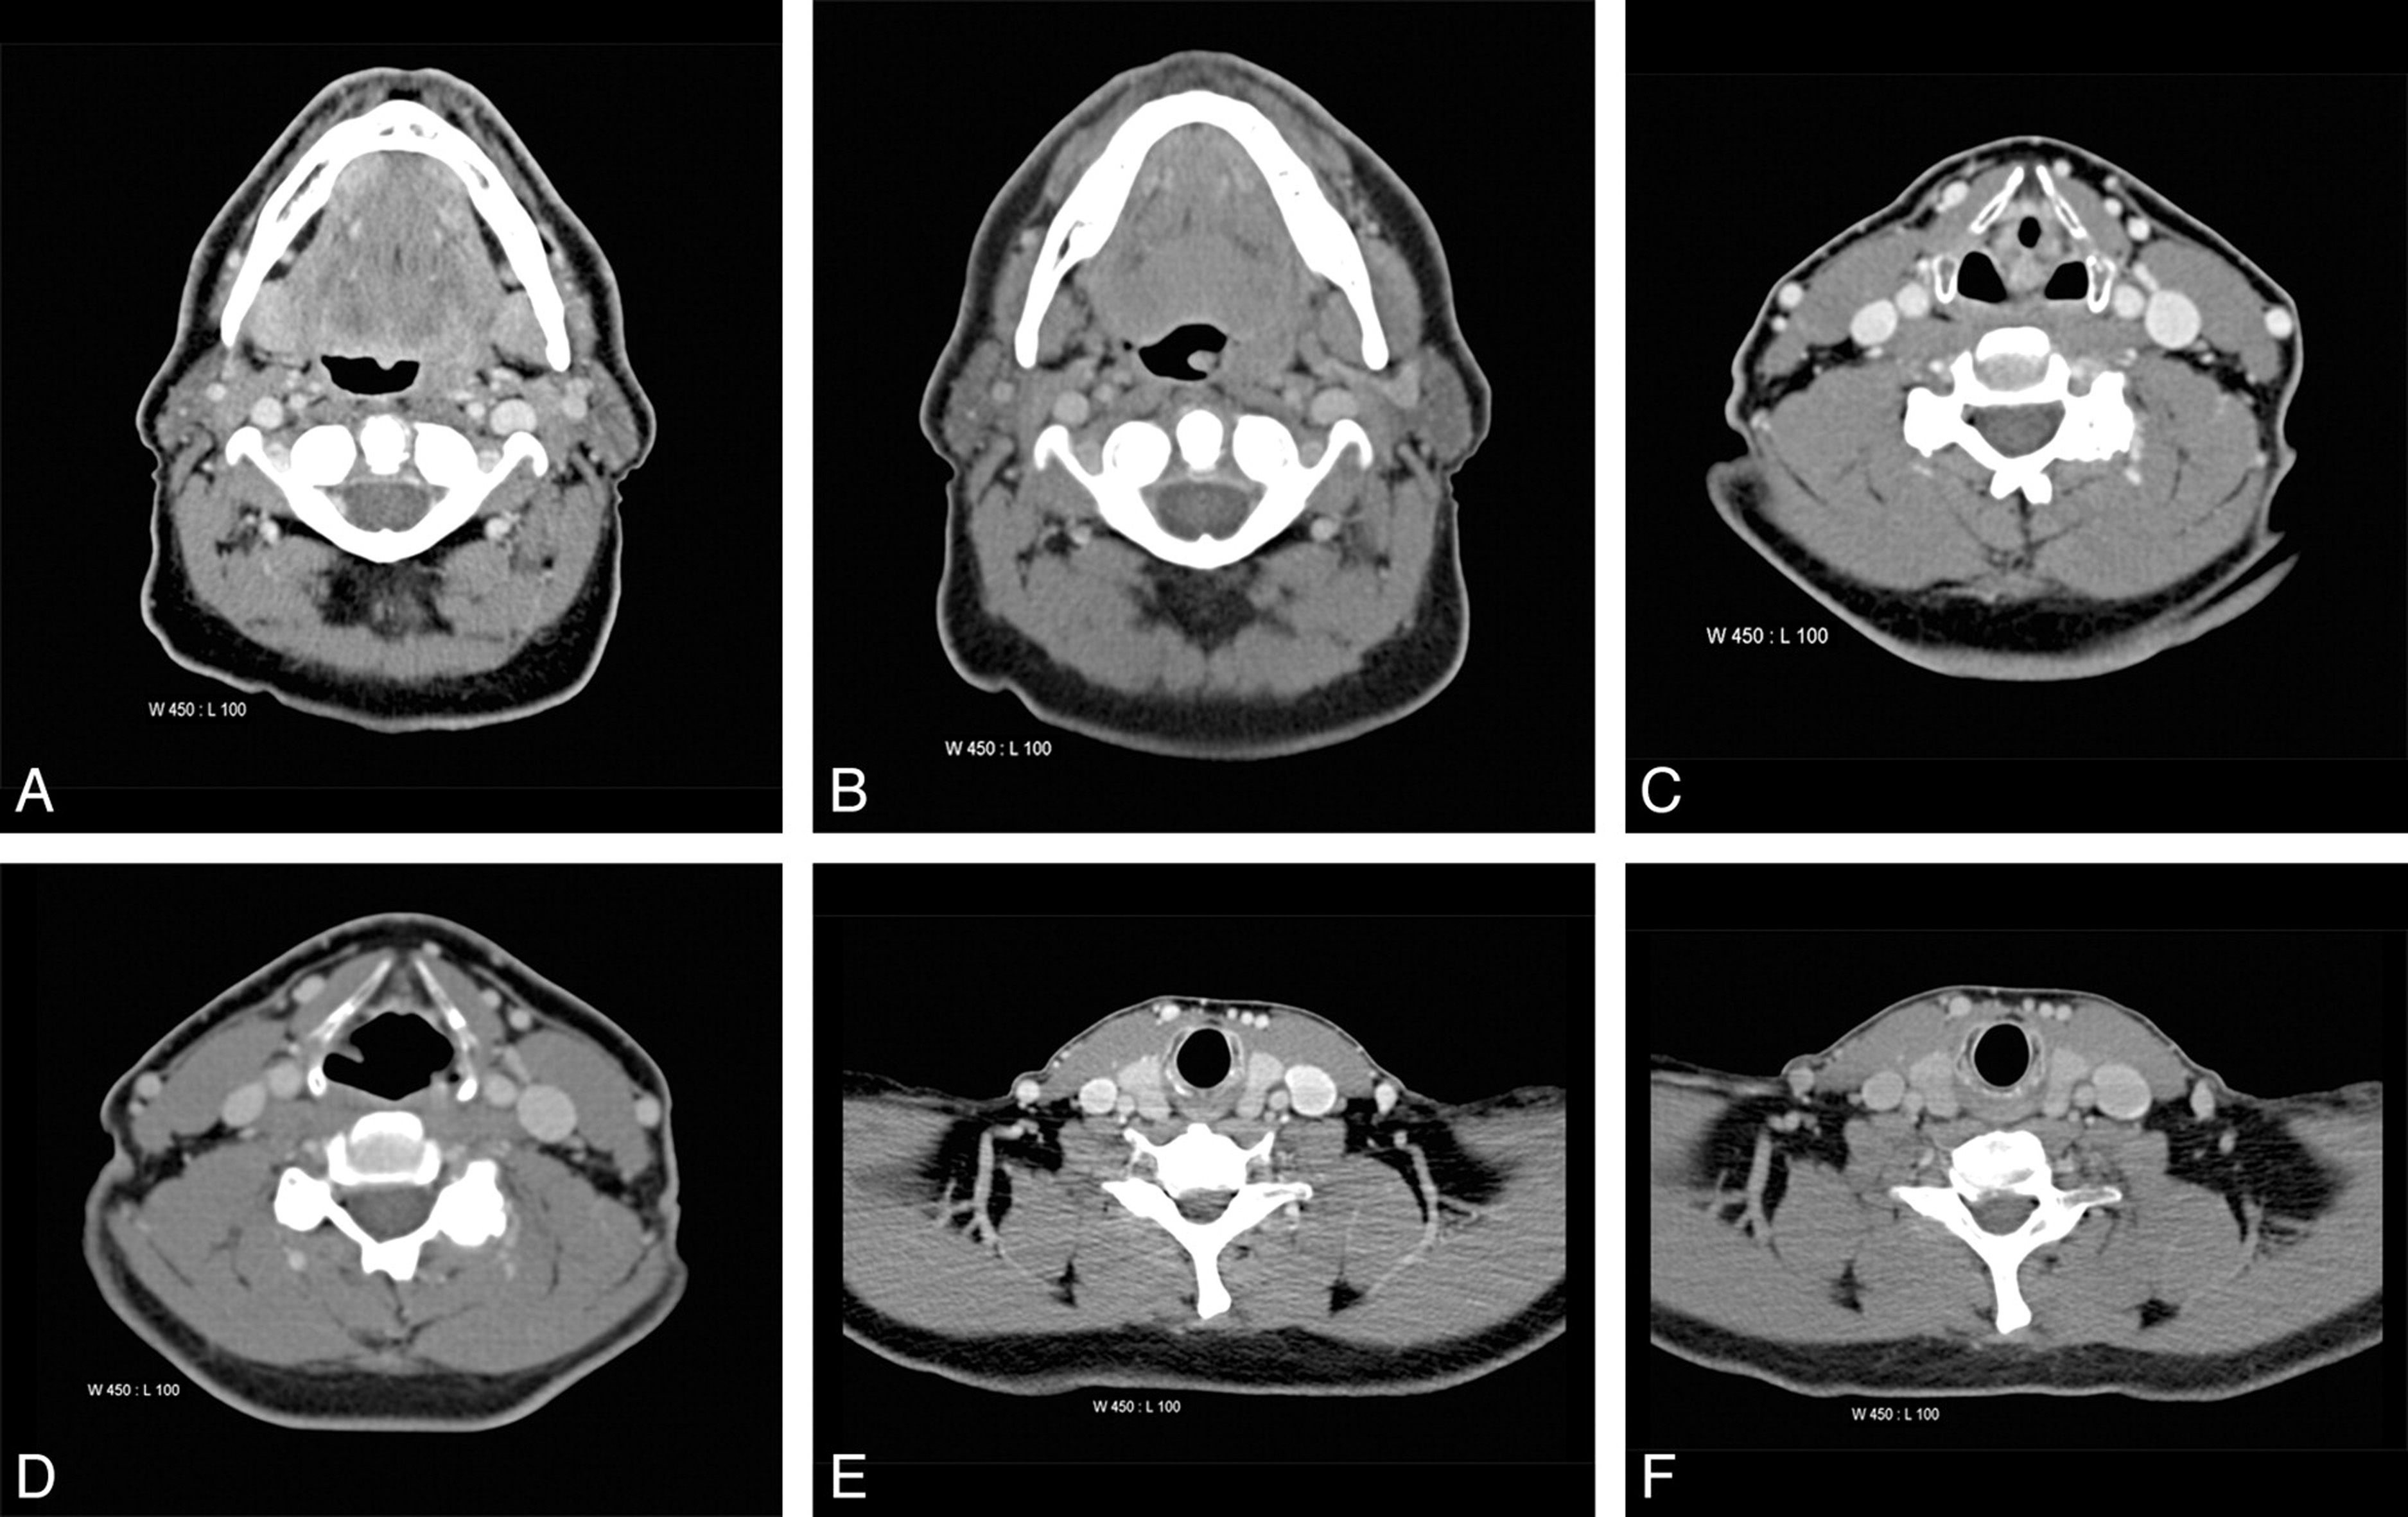

如当骨折发生时,X射线就像是一束神奇的光,穿透身体,将骨骼的影像清晰地呈现在胶片或数字探测器上,帮助医生迅速定位骨折位置,判断骨折类型,从而制定出科学的治疗方案。而CT扫描则更加精细,它从不同角度对身体进行X射线扫描,通过计算机处理,生成身体内部的横截面图像,让脑出血、脑肿瘤等微小病变无处遁形。

病变诊断影像